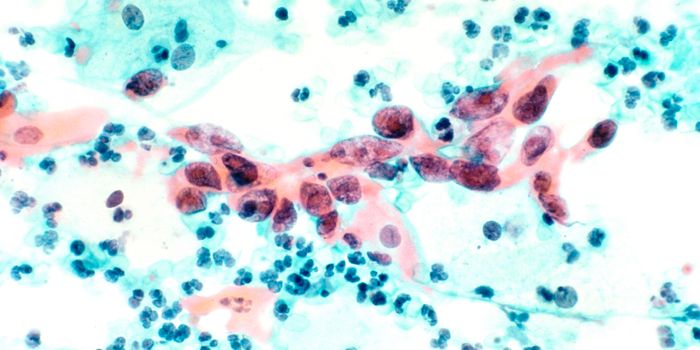

AUG 01, 2021Drug Discovery & DevelopmentA naturally-occurring compound called farnesol found in berries and other fruits prevents and reverses Parkinson's-a ...